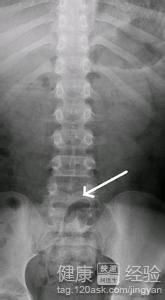

1這種症狀大多表現為脊椎後面有裂開的痕跡,椎間脊椎排列不整齊,骨盆不在原來的位置上,又或者脊椎的位置調換了等.但大部分外觀表現變化不大,而且輕微裂紋隱起來,不怎麼看的見,這種症狀大多在7歲以前明顯,過了七歲就會慢慢回歸正常,小孩尿床也明顯減輕了。

2如果7歲後還尿床大多數是與隱形脊柱裂沒有關系,因為假如說小孩到了6歲,再去檢查拍片,這種現象大大小小還是會有的,不會完全康復的,但是不要認為尿床真的與隱形脊柱裂有很大的關系,家長千萬不能認為這種病是不能治療的,不然會耽誤孩子的一生。